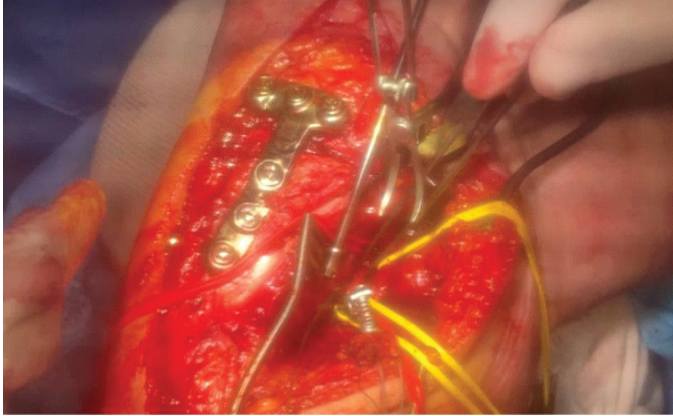

Figure 2: Intraoperative exposure during hematoma evacuation in Case 1. Intraoperative photograph of the posteromedial aspect of the knee during Case 1, taken immediately after surgical exposure for hematoma evacuation. Fixation hardware from the prior ligament reconstruction is visible along the medial femoral condyle. The organizing hematoma adjacent to the posteromedial portal exerted external compression on the popliteal artery, producing loss of distal Doppler signals before exploration. After evacuation of the hematoma, distal arterial pulses and Doppler signals were restored, confirming the absence of direct arterial injury. Vessel loops and retractors are shown maintaining exposure during decompression.

Although initially interpreted as arterial spasm, the clinical course suggests that external compression from the hematoma likely contributed to signal loss. The presence of preserved popliteal flow on duplex, followed by pulse restoration after hematoma evacuation, supports this interpretation (Fig. 2).